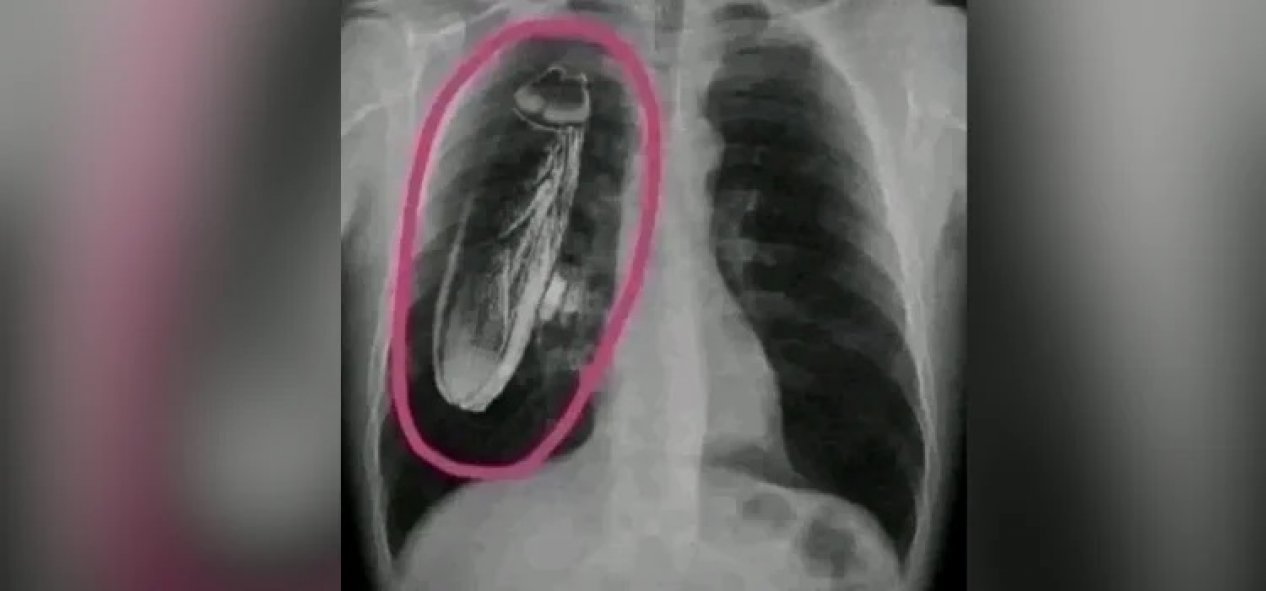

Fotoğrafta dijital müdahale var

İddiaya eklenen fotoğraf tersine görsel arama yöntemiyle arandığında, “hamam böceğinin” fotoğrafa sonradan eklendiği anlaşılıyor. Fotoğrafın aslı standart bir göğüs röntgeni.

İki görsel karşılaştırıldığında, böceğin sonradan eklendiği de görülüyor.